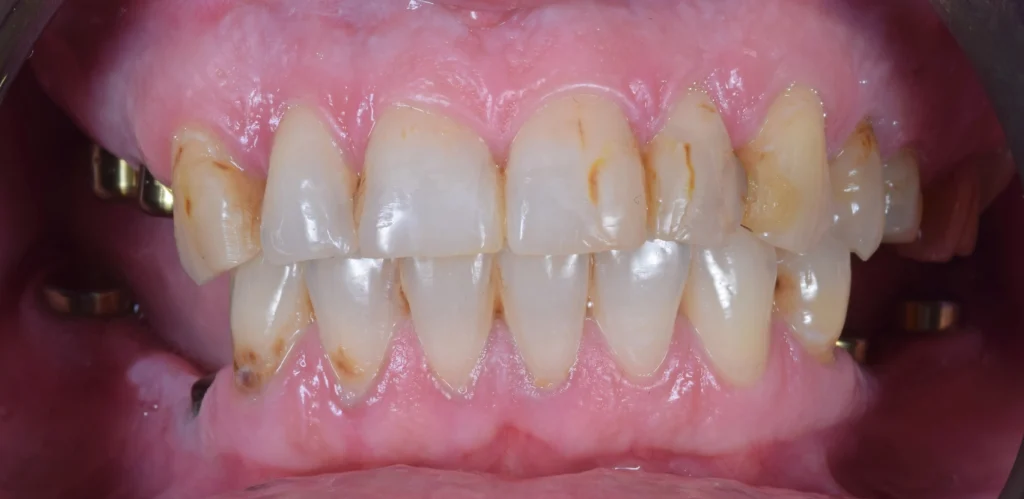

After the examination and the analysis, the therapy plan was full mouth reconstruction with dental implants and zirconia crowns and bridges. The remaining roots were extracted and six dental implants were placed using a surgical guide and digital workflow.

After the healing period of 6 months, the teeth were prepared and a prototype smile with provisional teeth was placed. After the analysis of the prototype smile, we made all the changes need to provide this patient with this new beautiful smile with zirconia crowns and bridges over the dental implants.